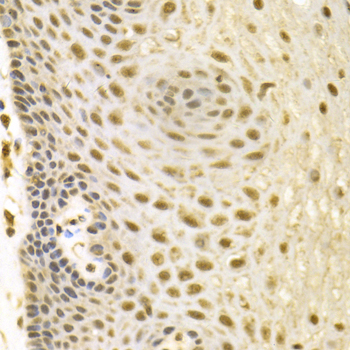

Immunohistochemistry of paraffin-embedded human esophageal cancer using BAG1 antibody at dilution of 1:100 (x400 lens).